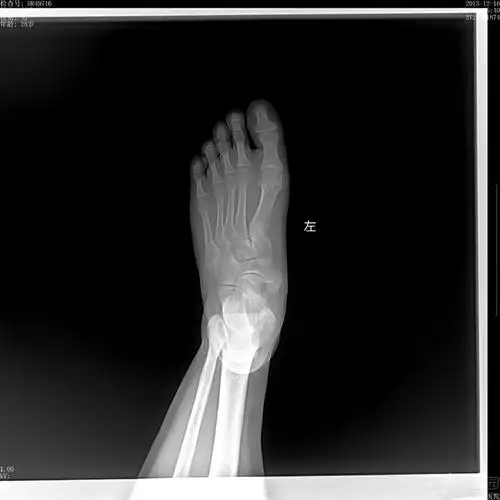

【读片】左足舟骨改变,大家怎么看?